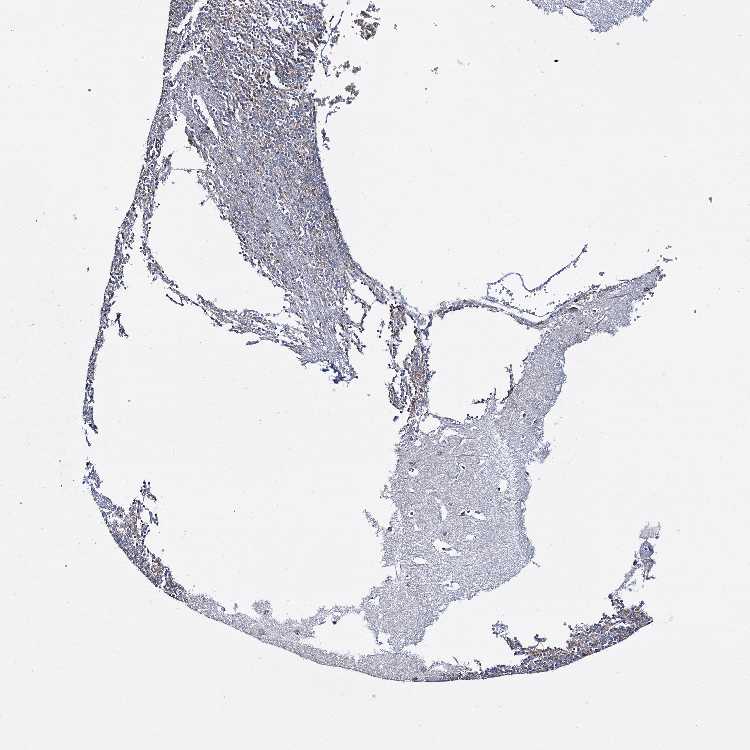

CEREBELLUM - Antibody stainingi

Antibody staining in the annotated cell types in the current human tissue is reported as not detected, low, medium, or high, based on conventional immunohistochemistry profiling in selected tissues. This score is based on the combination of the staining intensity and fraction of stained cells.

Each image is clickable and will lead to virtual microscopy that enables deeper exploration of all samples and also displays staining intensity scores, fraction scores and subcellular localization as well as patient and tissue information for each sample.

Antibody HPA039689

Purkinje cells Not detected

Cells in granular layer Low

Cells in molecular layer Not detected